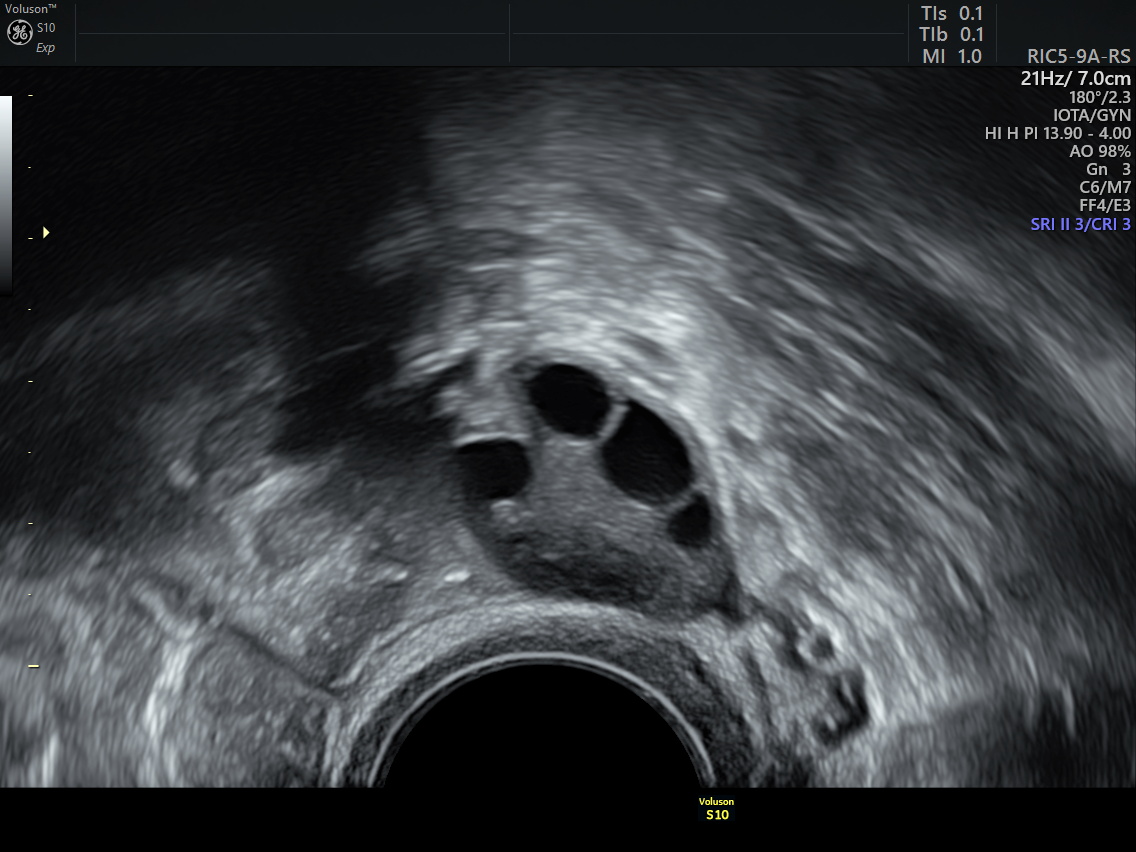

Ensuite, pendant les différents protocoles d’AMP (stimulation ovarienne, insémination artificielle, Fiv, Tec), l’échographie est un examen que nous réalisons très fréquemment afin de suivre la bonne marche du protocole. Cela nous permet d’observer notamment l’évolution de l’endomètre et des ovaires.

Afin d’assurer une bonne qualité des images et des mesures, cet examen est très souvent réalisé par voie vaginale. Il vous est demandé de venir à votre rendez-vous vessie vide.